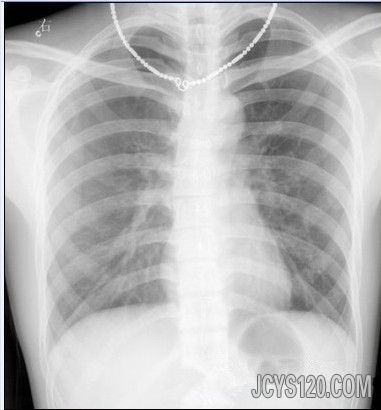

[size=5] 患者男,45岁。主述突感胸闷胸痛;呼吸困难30分钟。

该患者在今晨40分钟前进行户外跑步锻炼大约10钟后,突感胸闷胸痛,进行性加重,并出现呼吸困难及全身冷汗。被路边熟人发现急送我院,查;P102次/分 R26次/分 T36.2度 BP120/80毫米汞柱。查体,端坐呼吸,两肩耸起,精神状态欠佳,呈急性病容,口唇轻度紫绀,颈静脉无怒张,气管略向左移位。患者右侧胸廓略显饱满,但查无畸形,皮下无捻发音,无握雪感,左肺呼吸音清,未见异常罗音。右肺中上部分呼吸音消失,语颤音减弱,叩诊呈鼓音,心音纯率齐,102次/分,各个瓣膜未闻及杂音。腹部个压痛点未见异常,生理反射纯在,病理反射未引出。

心电图检查示:HR102次/ min,RR均齐,P- R间期,QRS时限,Q- T间期均在正常范围,P波电压>0 。2 5m V,QRS波两种形态交替出现,ST- T无明显异常,嘱患者闭气后描记心电图。QRS波呈一种形态,电交替现象消失

胸片;